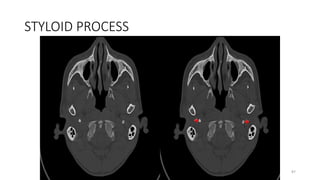

STYLOID PROCESS

87

96

106